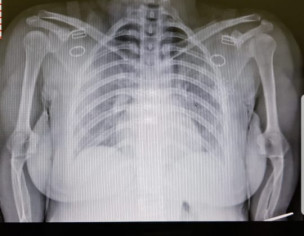

There are some deformities in the bones as seen in the xrays, would want to know about it

Developmental dysplasia of hip bilateral. (DDH). Google it u will know all about it.

there us generalised deformity of all bones and looks shortening as well and Development dysplasia of hip . looks achondroplasic

this is achondroplasia variant of AMC.